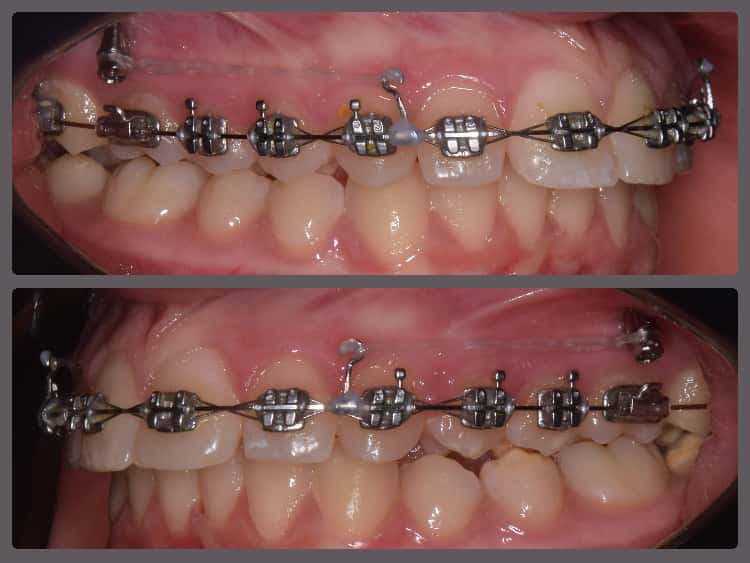

Balázs súlyos alsó torlódása miatt keresett fel magánrendelésemen. A diagnosztikus vizsgálatok során előbbin túl alsó-felső fogívszűkületet, valamint nyitott harapási hajlamot állapítottam meg. Kezelését Pitts21 alsó-felső rögzített fogszabályozó készülékkel kezdtük meg. A nyitott harapási hajlamot a hátsó fogakra helyezett harapásemelővel kontrolláltuk. A torlódott fogaknak tolórugóval és interproximális redukcióval teremtettünk helyet, és intermaxilláris gumihúzással tökéletesítettük a harapást. A fogszabályzó kezelés teljes időtartama alatt Balázs 110%-osan együttműködő volt, ezért 21 hónap alatt sikerült kiemelkedő végeredményt elérnünk.